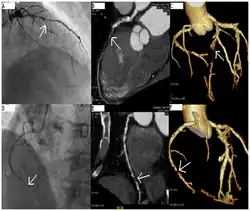

Alternative approaches

CT angiography can act as a less invasive alternative to Catheter angiography. Instead of a catheter being inserted into a vein or artery, CT angiography involves only the injection of a CT-visible dye into the arm or hand via an IV line. CT angiography lowers the risk of arterial perforation and catheter site infection. It provides 3D images that can be studied on computer, and also allows measurement of heart ventricle size. Infarct area and arterial calcium can also be observed (however those require a somewhat higher radiation exposure). That said, one advantage retained by Catheter angiography is the ability of the physician to perform procedure such as balloon angioplasty or insertion of a stent to improve blood flow to the artery.[8]